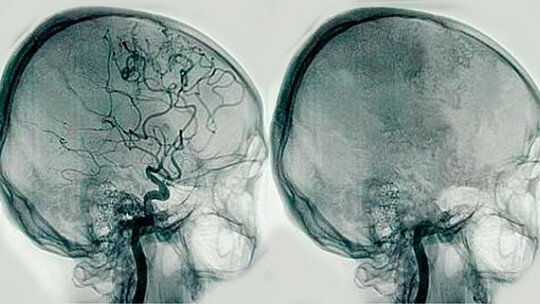

Angiografía por contraste radiopaco

Surge la angiografía por contraste radiopaco para diagnosticar trastornos cerebrales, tumores y malformaciones vasculares.